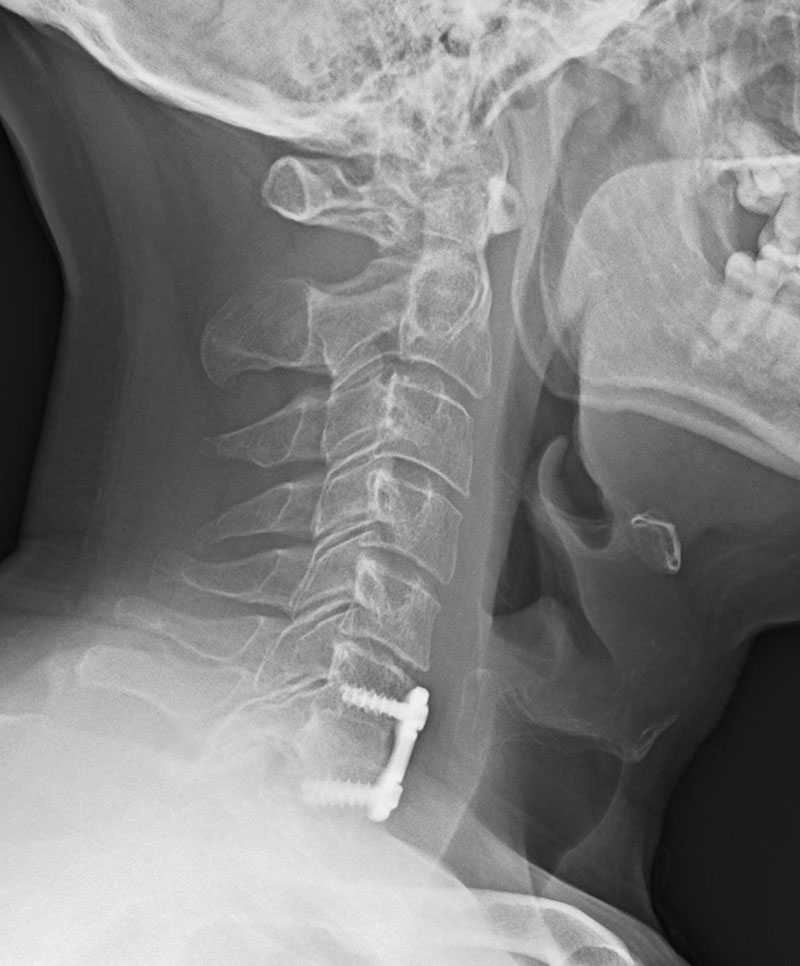

Therefore spinal hardware eg. One of the best signs for pseudoarthrosis failed fusion is a halo formation on the x-ray or CT scan. Finally how well does it work to try a different approach when treating failed fusions.

If there is an issue with your implanted spine hardware your physician will first confirm with an x-ray or other imaging scan. The cause of failed cervical fusion surgery can vary considerably with possibilities that include. If the fusion doesnt happen as it should pseudoarthrosis the screws can loosen.

Pedicle screws may be used as an internal splint to hold the spine while it fuses after spine surgery.